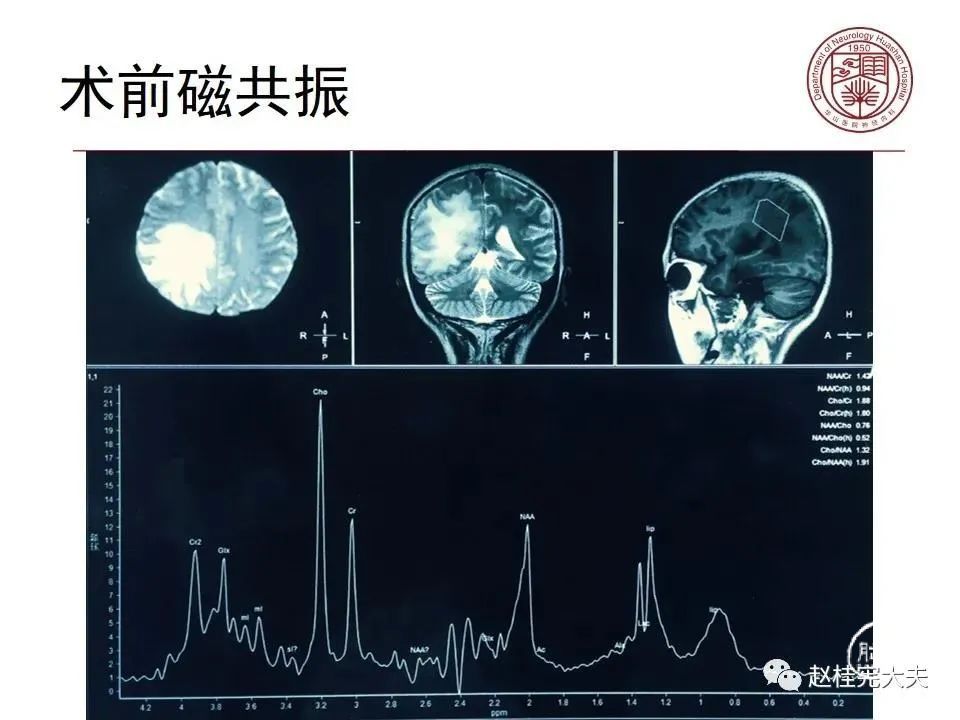

病例3